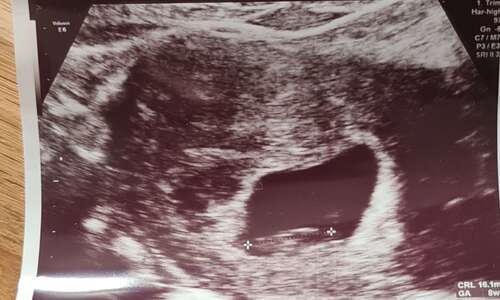

Echo 26/10/2023 - 5+6 weken zwanger volgende week maandag 06/11/2023 nieuwe echo 7+3 weken dan zwanger